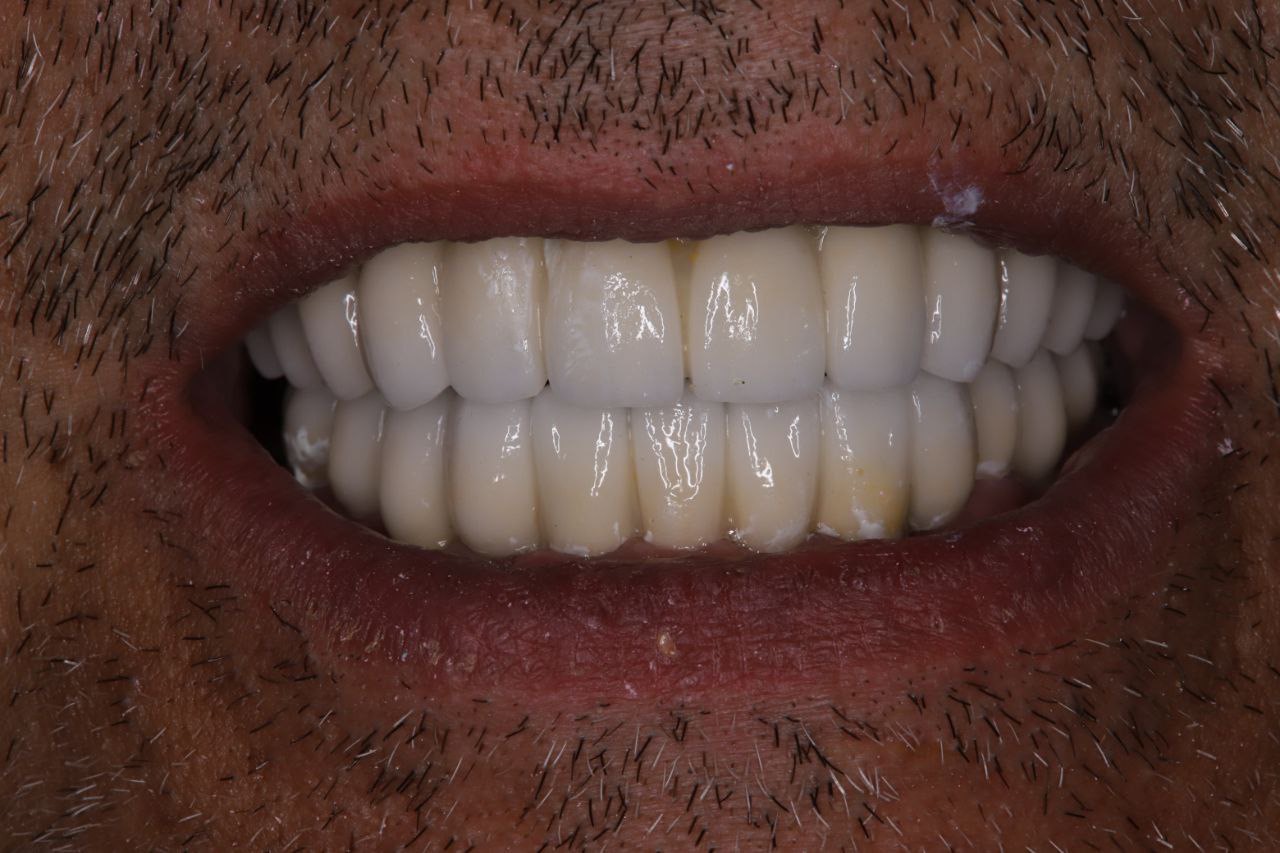

Результат проделанной работы

Пациент обратился с полным отсутствием зубов.

Установлено 6 дентальных имплантов. После хирургического этапа были изготовлены и зафиксированы временные коронки (временная ортопедическая конструкция) на период приживления имплантов. После завершения остеоинтеграции изготовлены и установлены постоянные коронки из диоксида циркония.

Результат — восстановлены функция жевания и эстетика улыбки.